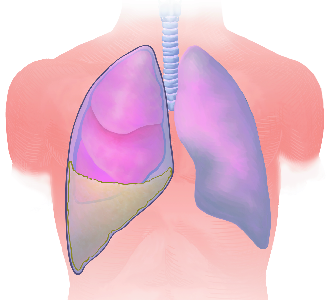

Detailreiche Fotografien aus der medizinischen Praxis ergänzen die Texte; moderne, genaue,

wissenschaftliche Zeichnungen geben Einblick in die Anatomie und die Funktion der Lunge und

anderer Organe.